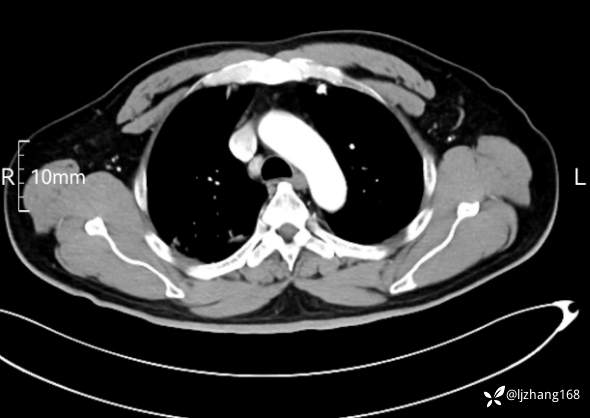

中年男患,右肺团片影,炎症0R肿瘤?

简要病史: 20+天前患者因受凉后出现阵发性咳嗽,咳少量白色粘痰,痰易咳出,伴活动后气短,伴纳差、乏力、全身酸痛,伴多汗,无痰中带血及咯血,无发热、畏寒及寒战,无潮热、盗汗,无夜间阵发性呼吸困难及端坐呼吸,无声嘶,无头晕、头痛,无黑矇、晕厥及意识障碍,无腹痛、呕血及黑便等不适,遂就诊于当地医院予以输液等治疗后未见明显好转(具体诊疗不详),现为进一步诊治就诊于我院门诊,以“右肺占位”收入我科。病来饮食欠佳,近期体重下降(具体不详)。既往糖尿病病史7+年,未规律监测血糖,血糖控制不佳。否认“高血压、冠心病及慢性肾脏病”等慢性疾病史。否认“肝炎、结核、伤寒”等传染病史。否认食物、药物过敏史。否认外伤、输血史,预防接种史不详。

辅助检查:糖化血红蛋白12.3%。肺炎支原体IgG、IgM、呼吸道合胞病毒均未见明显异常。胸部CT:右肺上叶阻塞性肺炎。